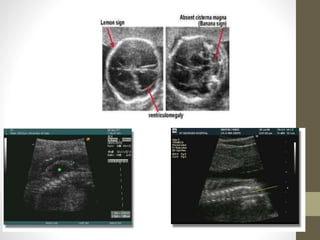

Ventriculomegaly

US Findings:

>10 mm diameter

> 3 mm choroid seperation

from medial wall

โ€œdangling choroidโ€

Choroid plexus Hangs

independently from

ventricle

Chiari II Malformations

โ€ข See in 95% of Myelomenigoceles

โ€ข Abnormalities Include:

โ€ข 1. Caudal displacement of

โ€ข CEREBULLUM

โ€ข Pons

โ€ข Medulla

โ€ข 2. 4th Ventricle Elongated

โ€ข 3. Posterior Fossa small

โ€ข 4. Beaking of Tectum

โ€ข 4. Cisterna Magna

โ€ข Obliterated

Spina Bifida

โ€ข Most Common: Lumbosacral

โ€ข Can occur anywhere in spine

โ€ข US Findings:

โ€ข Outward Splaying of Laminae

โ€ข Soft Tissue Defect

โ€ข overlies bony defect

โ€ข Protruding Sac (+/- neural tissue)

โ€ข +/- Chiari II Malformation

โ€ข +/- Ventriculomegaly (75%)

โ€ข Banana Sign

โ€ข Cerebellar hemispheres squashed

into shape banana

โ€ข Cisterna Magna is small or gone

โ€ข Lemon Sign

โ€ข Bossing of frontal bones

โ€ข Lemon shaped head on axial scan